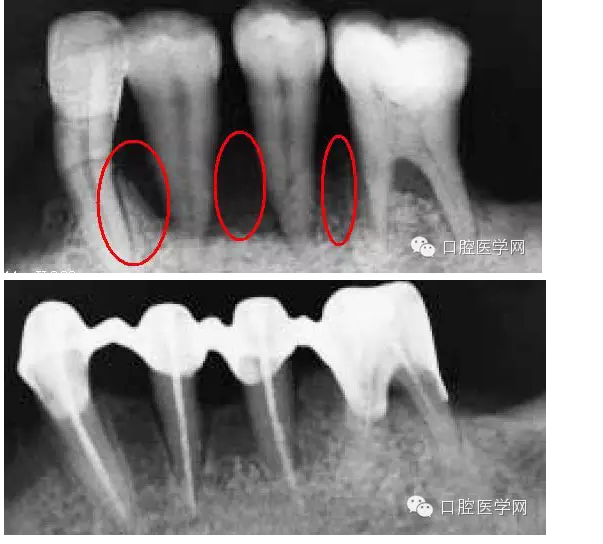

這里先發(fā)一張照片,是一個需要解決黑三角的病例。照片是在一國外文獻上截的(我很少看國內(nèi)的文獻)。從照片上看,患者前牙去區(qū)基本都有黑三角的問題。那么是為什么會出現(xiàn)黑三角?

接上面的照片發(fā)一張X-RAY,從圖片中大家應該能看到,骨已經(jīng)吸收了,所以骨喪失是牙齦乳頭吸收最主要的原因——牙周區(qū)的紅色美感是依靠骨來支持。

但是,并不是所有的牙齦退縮都是無法在恢復的。一些患者在去除刺激物包括炎癥,骨是可以基本恢復原來的健康的(或者說恢復一些)。當然你要通過X-RAY分辨出骨的吸收情況是什么樣。如果象上面第一個病例那張X-RAY那樣,水平吸收嚴重就別想了。但如果是下圖這樣,牙齒周圍還保留有骨壁,只要去除炎癥、不良修復體和調(diào)整咬合情況,骨是可以恢復的。所以,齦乳頭黑三角最好拍張X-RAY去看看骨的情況,而醫(yī)生不只是對牙周,同時對其他學科也應該有些了解。